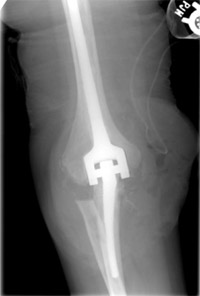

X-ray of a patient who underwent elbow joint replacement.

When nonsurgical interventions are not enough to control symptoms, surgery may be needed. By the time arthritis can be seen on X-rays, there has been significant wear or damage to the joint surfaces. If the wear or damage is limited, arthroscopy can offer a minimally invasive surgical treatment. It may be an option for patients with earlier stages of arthritis.

If the joint surface has worn away completely, it is unlikely that anything other than a joint replacement would bring about relief. There are several different types of elbow joint replacement available.

In appropriately selected patients, the improvement in pain and function can be dramatic. With an experienced surgeon, the results for elbow joint replacement are typically as good as those for hip replacement and knee replacement.